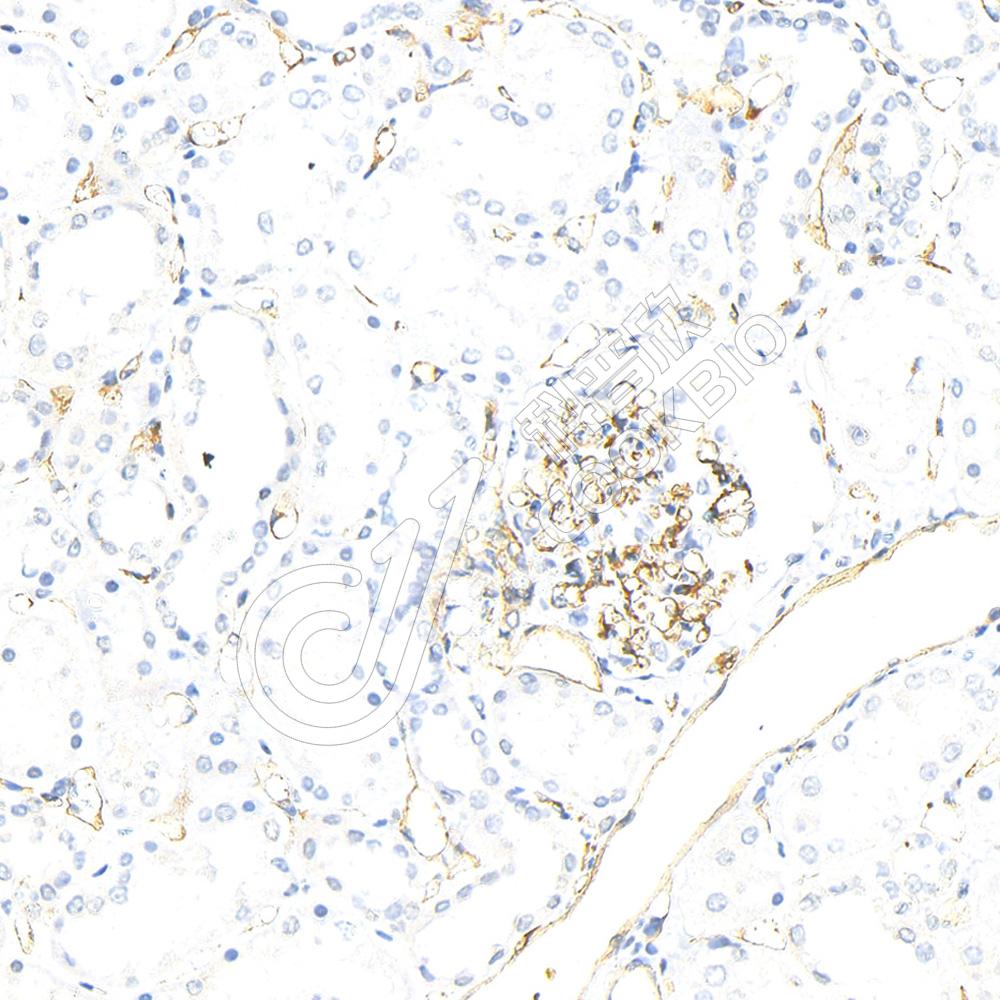

IHC检测CD63蛋白(货号 K1347136).

样品: 小鼠脾, 4%多聚甲醛 (货号KSG1101) 固定12-24小时.

抗原修复: 柠檬酸抗原修复液(干粉, pH 6.0) (KSG1201), 98℃, 20分钟.

—抗: 1: 1000稀释, 4℃ 孵育过夜.

二抗: S-vision免疫组化多聚二抗(山羊抗兔),即用型 (货号KB3906), 室温孵育20分钟.